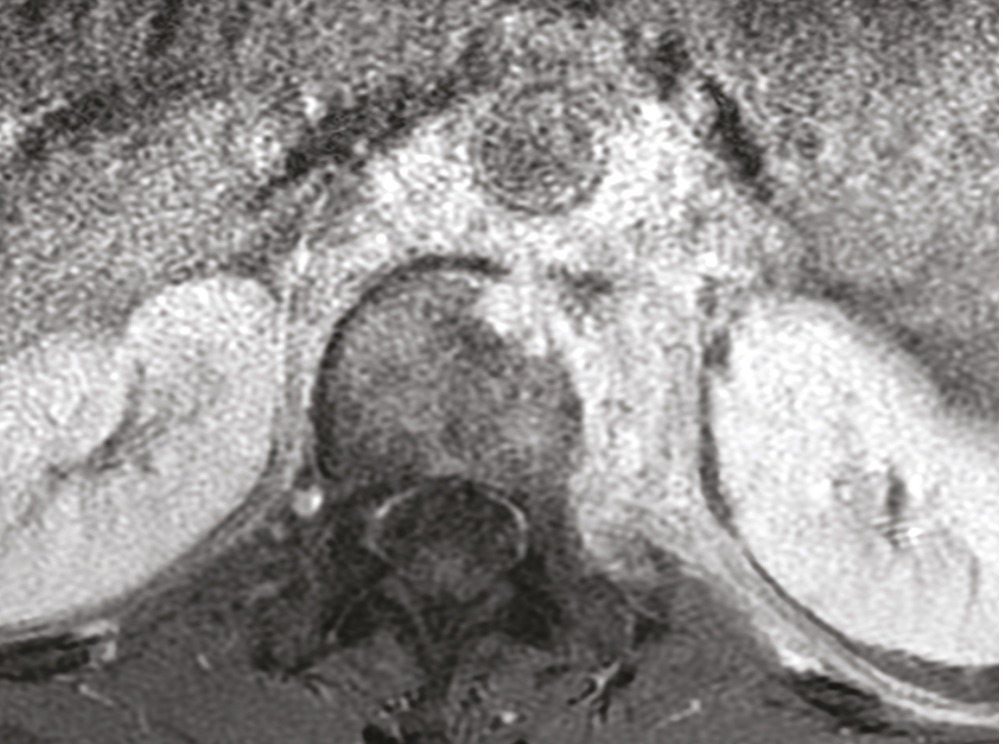

Cet homme de 53 ans consultait pour une douleur de la charnière dorsolombaire à irradiation antérieure, mal calmée par les antalgiques, avec un amaigrissement sans fièvre. L’examen clinique trouvait une raideur rachidienne et le bilan biologique montrait un syndrome inflammatoire. La tomodensitométrie (TDM) abdominale révélait une fibrose rétropéritonéale avec lyse de L1 (fig. 1 ). L’imagerie par résonance magnétique (IRM) montrait un aspect de fibrose rétropéritonéale secondaire, en hyposignal T1 et T2, se rehaussant après injection du gadolinium avec lyse de L1 (fig. 2 ). La tomographie par émission de positons au 18-fluorodésoxyglucose (TEP18-FDG) montrait un hypermétabolisme intense de L1 dont la biopsie scannoguidée révélait un granulome épithélio-giganto-cellulaire cadrant avec une tuberculose (fig. 3 ). Le patient était efficacement traité par les antibacillaires pendant 9 mois.

Figure 1. TDM, coupe axiale, fibrose rétropéritonéale refoulant l’aorte en avant avec lyse de L1.